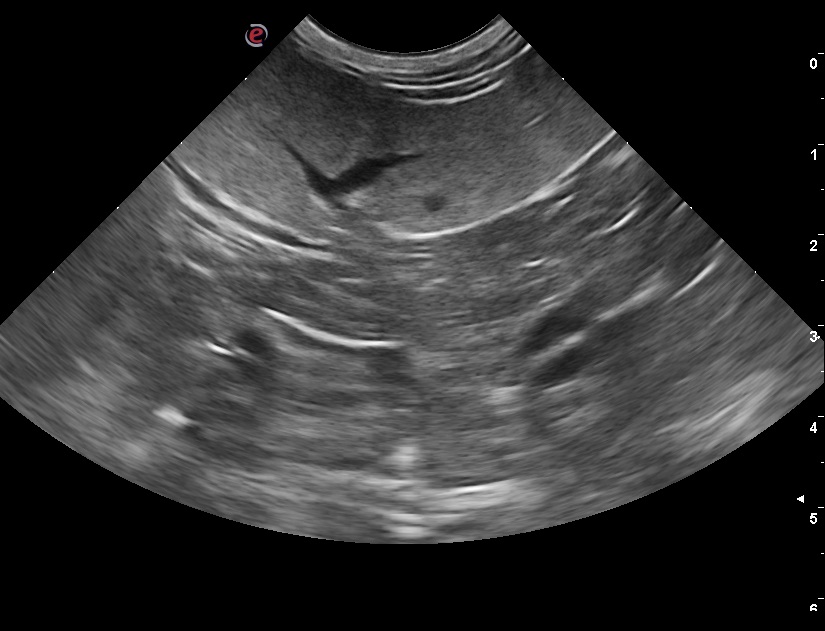

Ecoaddome del cane e del gatto, diagnosi e monitoraggio della gravidanza, centesi endocavitaria, citologia ecoguidata.

Lavoro dal 2018 come veterinaria, occupandomi principalmente di medicina interna del cane e del gatto ed ecografia addominale.